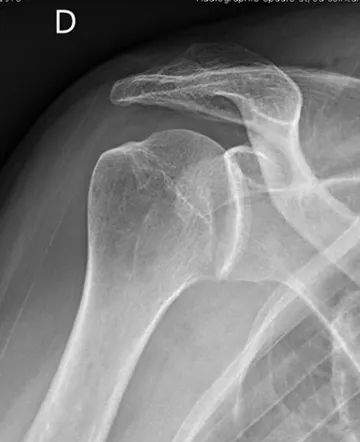

QUELS SONT LES EXAMENS COMPLÉMENTAIRES À RÉALISER ?

Dans un premier temps des radiographies permettent d'avoir une orientation diagnostique en corrélation avec l'examen clinique du chirurgien. Il s’agit du bilan de débrouillage qui sera complété le plus souvent par un arthro-scanner ou une IRM.